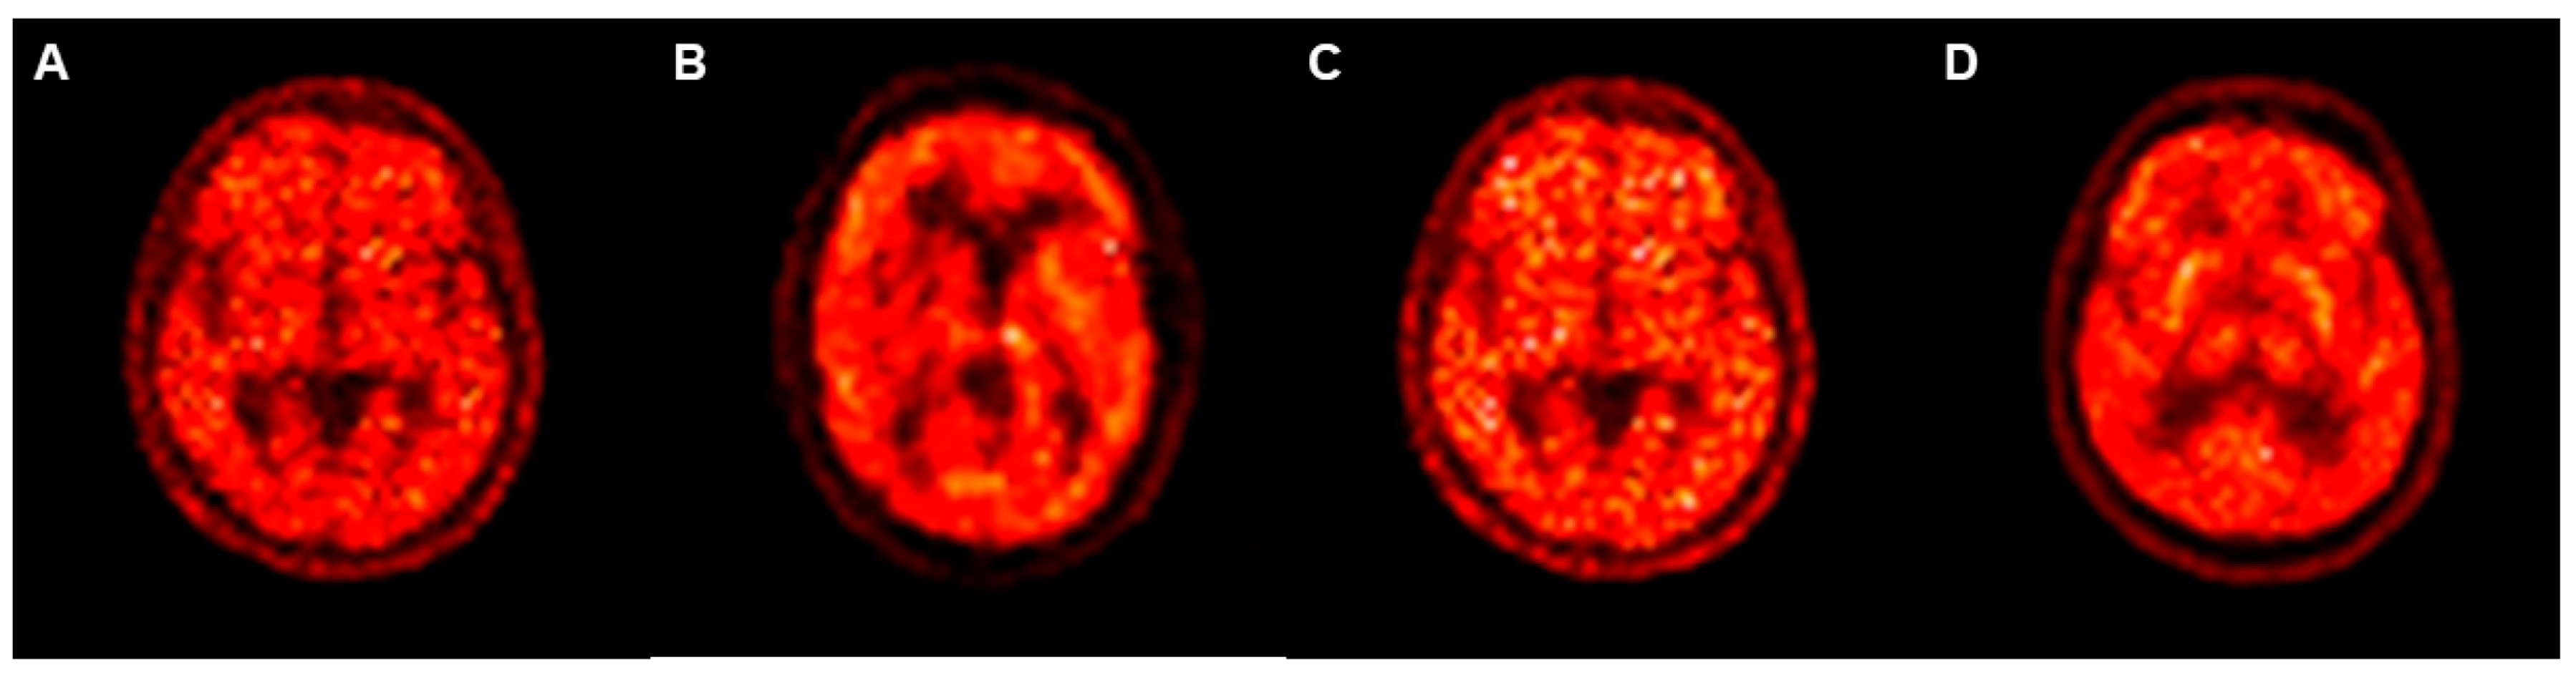

| CycleGAN Model | Pix2pix Model | p Value * | |

|---|---|---|---|

| Mean | 0.768 | 0.745 | <0.001 |

| Standard deviation | 0.135 | 0.143 |

| Mean | 32.4 | 30.7 | <0.001 |

| Standard deviation | 9.5 | 8.0 |